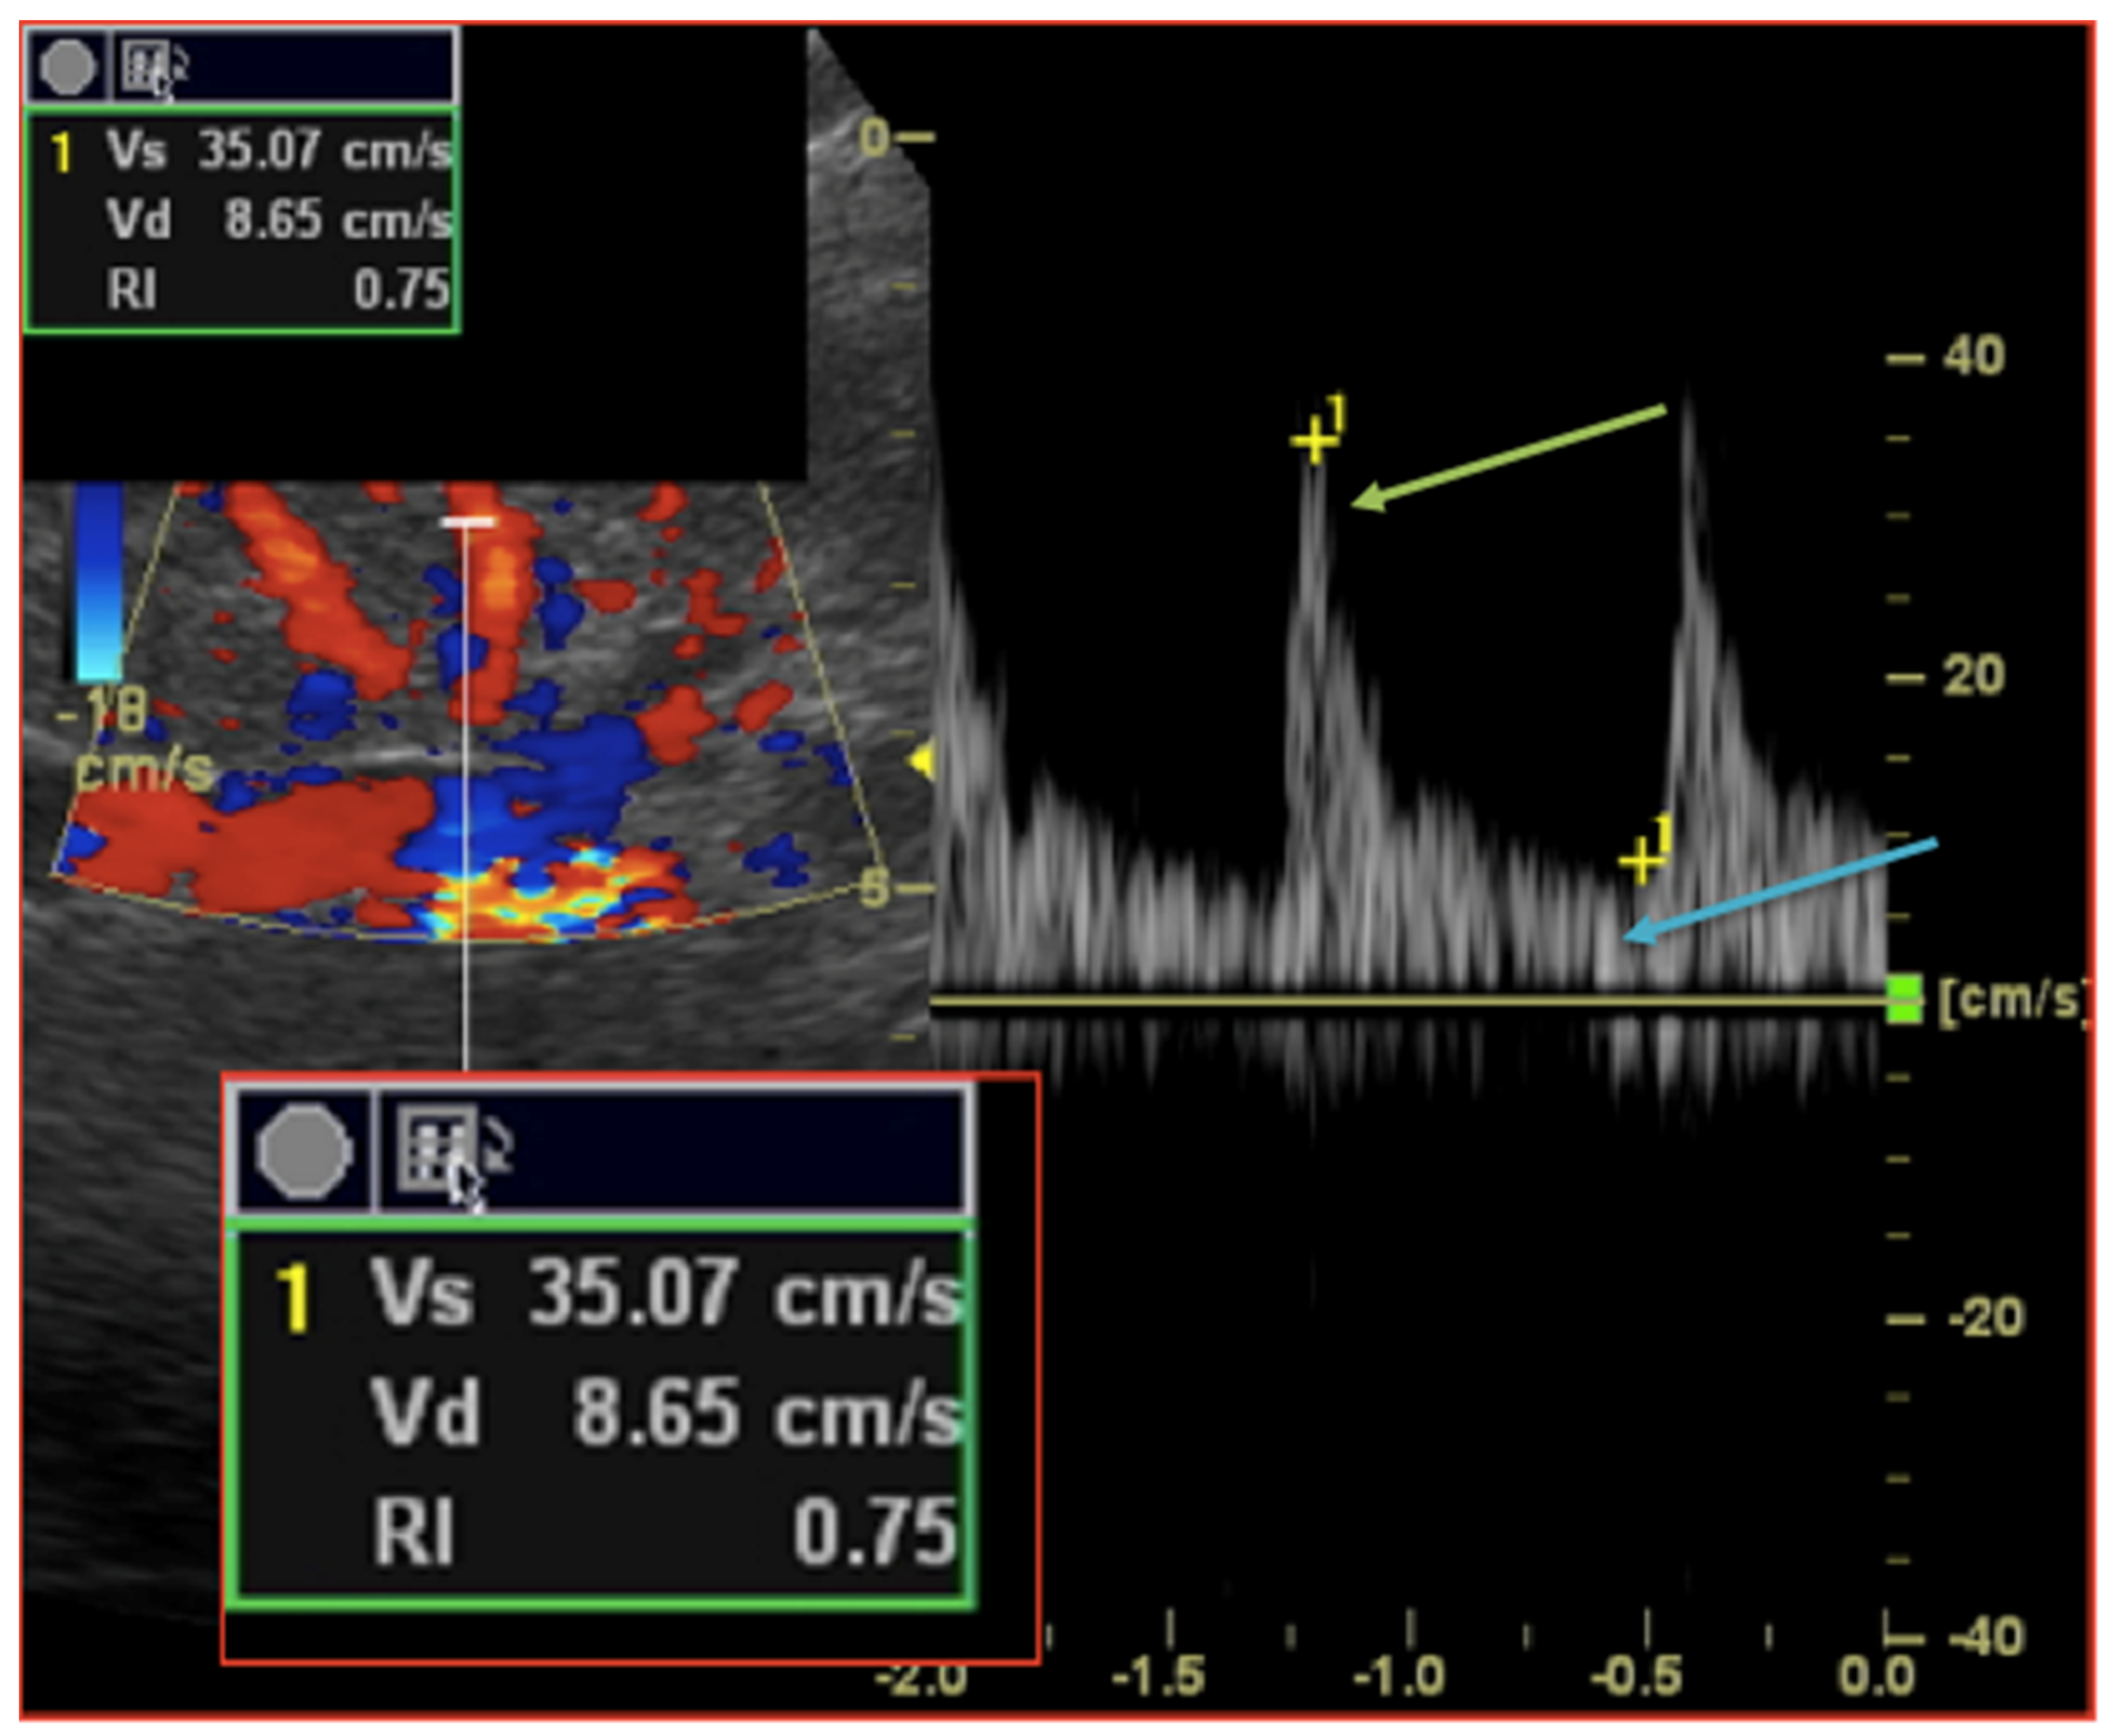

- Doppler based renal resistive index (RRI) measurements is a rapid and non-invasive method proposed for early AKI detection

- 24 h post-TAVR evaluation by Doppler-based resistive index is associated with AKI occurrence up to day 3

- Doppler based renal resistive index is an easy, objective, reliable and low-cost tool that succeeded to identify an at-risk population for AKI and able to improve the post TAVR management